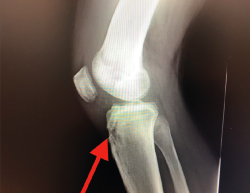

El tratamiento de un paciente que sufre una rotura aguda del LCA (Figura 2) sigue siendo motivo de discusión(9). Hay muchos condicionantes que influyen en el manejo terapéutico de estas lesiones (ya sea quirúrgico como no quirúrgico), como son la edad, la ocupación, la actividad deportiva, las lesiones asociadas, el grado de laxitud de la rodilla, las expectativas o las recidivas de la lesión, entre otras. El riesgo de artrosis tras la rotura aguda del LCA será mayor en ambos grupos con respecto a la población sana, sea cual sea el tratamiento(12). Los factores de riesgo más importantes para el desarrollo de artropatía son: lesión meniscal, meniscectomía e injerto hueso-tendón-hueso (HTH).

Figura 2. Rotura aguda del ligamento cruzado anterior.